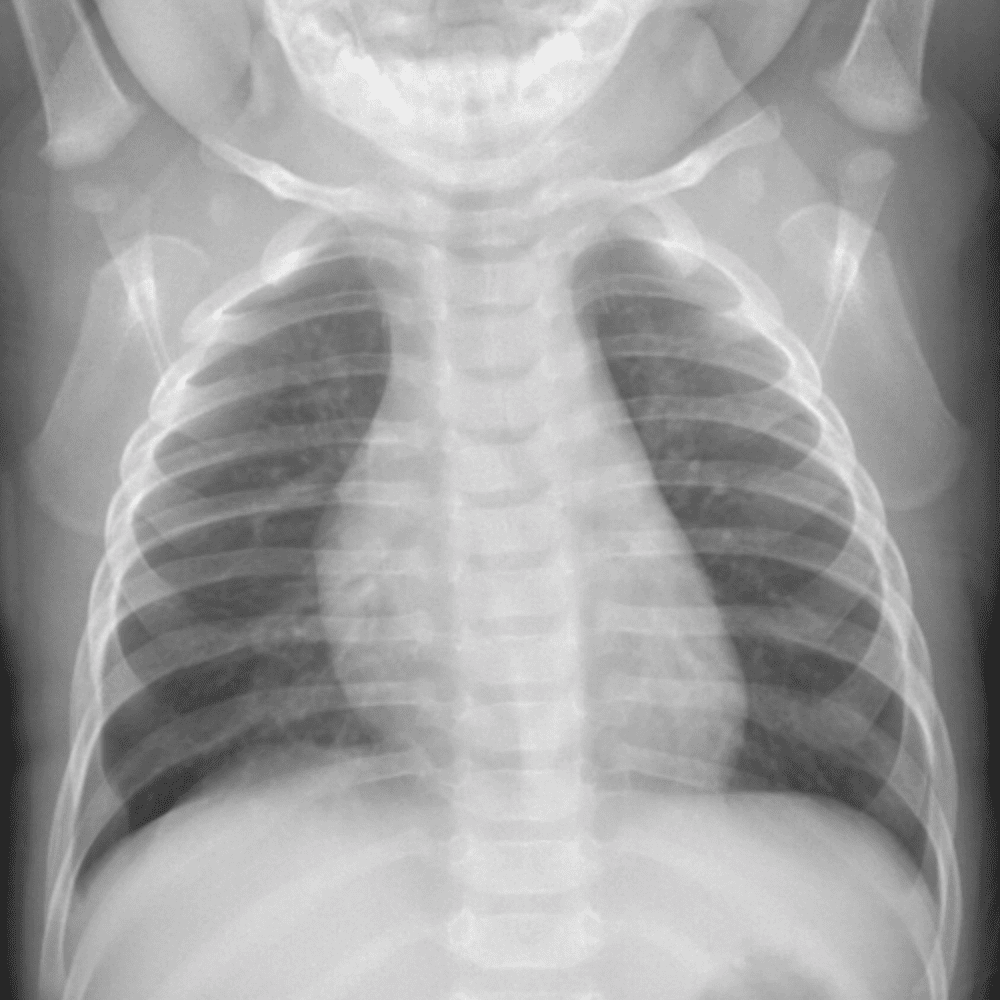

Peds Chest

Practice

Simulates call by including subtle or difficult cases and some normals.

50 cases